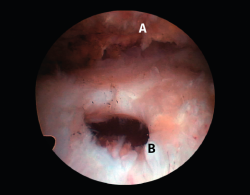

Figura 5. Rotura de tipo C1. A: rotura pequeña de espesor completo del supraespinoso; B: cabeza humeral.

Sin embargo, las clasificaciones basadas en el tamaño de la rotura deben ser bidimensionales, ya que la visión unidimensional puede ser engañosa, al mostrar el tamaño de la rotura solo desde el plano anteroposterior(4). Por esta razón, proponemos el sistema de clasificación del manguito posterosuperior sugerida por Snyder, que aporta información no solo del tamaño, sino del número de tendones afectados y la presencia de tejido cicatricial(7). En las lesiones de tipo C1 la lesión atraviesa todo el espesor del tendón y en el eje transversal es pequeña y punzante (Figura 5). Las de tipo C2 son roturas de espesor completo pero la distancia entre los extremos de la rotura es menor de 2 cm con escasa retracción (Figura 6). En las de tipo C3 la rotura afecta en sentido transversal entre 3 y 4 cm con mayor retracción implicando 2 tendones (Figura 7). Y las de tipo C4 son la rotura masiva del manguito de los rotadores con una afectación de espesor completo de toda la anchura de 2 o más tendones asociando importante retracción (Figura 8).